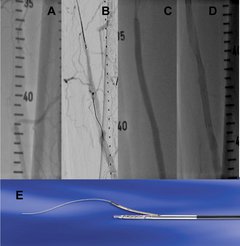

Schnelle Diagnostik bei chronischen Wunden - Angiographien und therapeutische Katheterinterventionen (PTA)

Diagnostik und Therapie von peripheren Arterien der oberen und unteren Extremitäten sowie der Bauchaorta und der Nierenarterien.